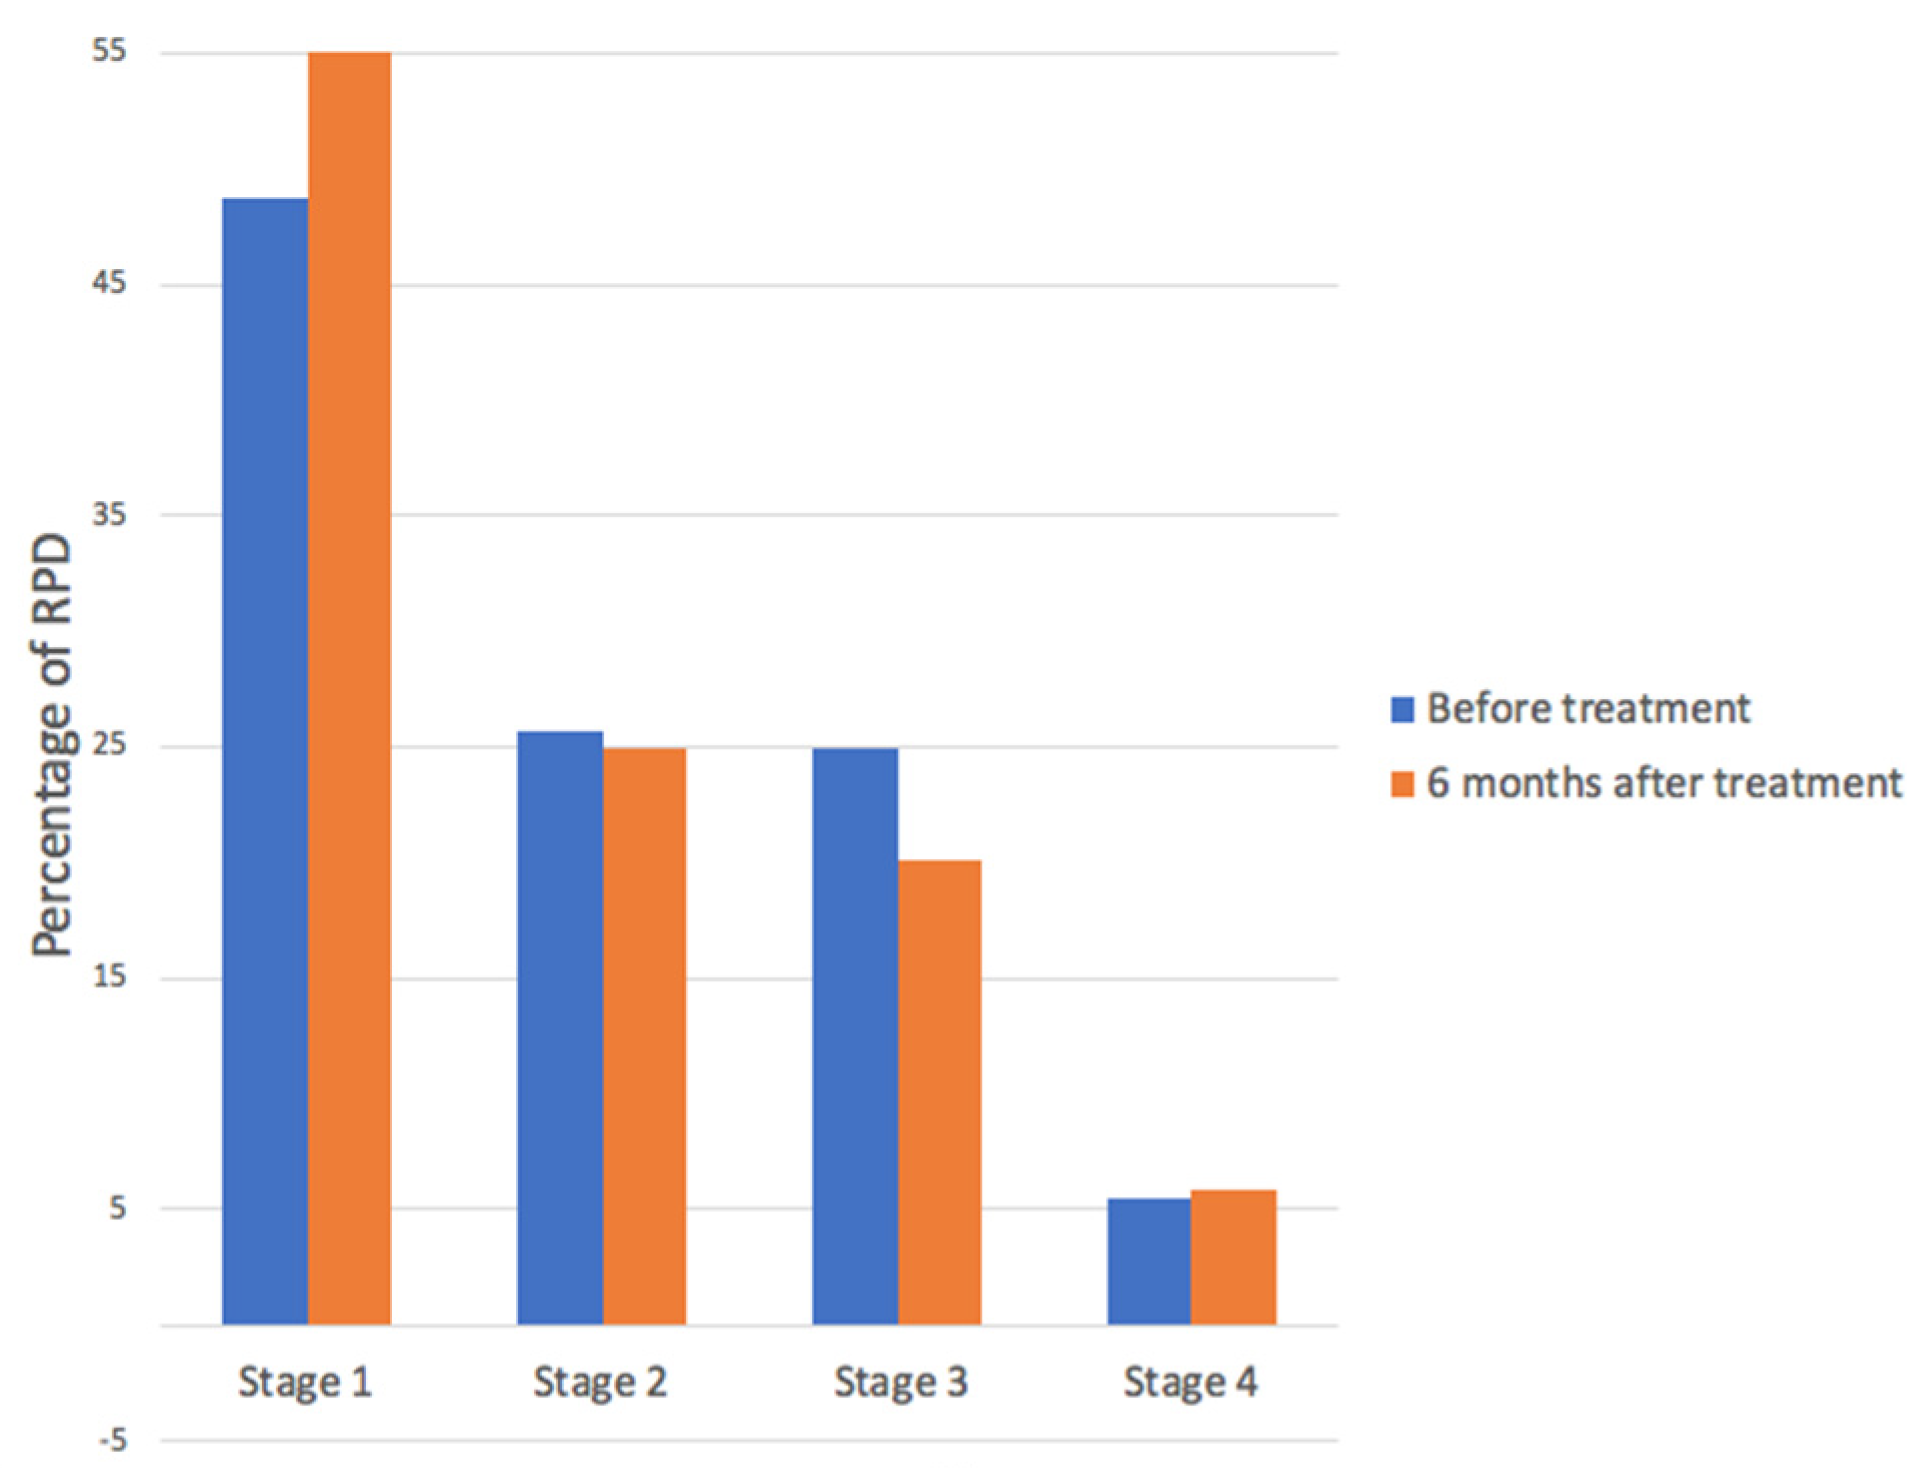

3. Results